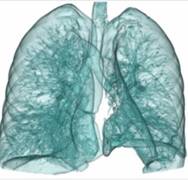

320排螺旋CT具备16cm宽覆盖探测器,实现动态容积扫描,360度的各向同性采集能力及[email protected]%密度分辨率的量子探测器,一次心跳全心脏采集,一圈扫描器官成像,一次检查完成多重任务,实现真正的动态容积体灌注及心脏、神经一站式检查;西门子Flash炫速CT扫描系统,具备两套同时旋转的X射线球管及探测器,实现了43cm/s的极快CT扫描速度和75 ms的时间分辨率,完成全胸扫描仅需0.6秒,使得患者做心脏扫描时无须食用β-受体阻滞药,亦无须屏气,并可实现低于1mSv的超低辐射剂量,配置第二代双能量、宽151级纯化能谱,组织鉴别能力进一步提高,可开展多达10余种双能量成像应用。

头颅一站式检查:320排容积CT覆盖范围达16cm,球管旋转一周可以覆盖整个脑组织,获得全脑0.5mm层厚各向同性全脑信息。一次扫描可以获得平扫容积图像、以时间为序列全脑动态3D-CTA图像(包括纯动、静脉期成像)及全脑灌注图像。一次检查即可排除脑出血、动脉瘤、动脉狭窄、梗塞、脑实质供血异常等多种病变及进行脑卒中筛查。